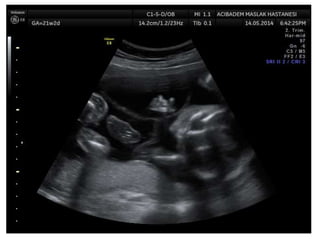

Amniotic band sequence:

Amniotic band sequence refers to a highly variable

spectrum of congenital anomalies that occur in

association with amniotic bands

Anomalies include:

Craniofacial abnormalities — eg, encephalocele, exencephaly,

clefts, which are often in unusual locations; anencephaly.

Body wall defects (especially if not in the midline), abdominal or

thoracic contents may herniate through a body wall defect and

into the amniotic cavity.

Limb defects — constriction rings, amputation, syndactyly,

clubfoot, hand deformities, lymphedema distal to a constriction

ring.

Visceral defects — eg, lung hypoplasia.

Other — Autotransplanted tissue on skin tags, spinal defects,

scoliosis, ambiguous genitalia, short umbilical cord due to

restricted motion of the fetus